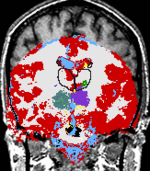

The temporal evolution of an MS lesion. See Meier et al. Neuroimage 2006 for more info.

The Multiple Sclerosis (MS) Project at Brigham and Women's Hospital was spun off the SPL in the mid-nineties and became fully operational in early 2000. The CNI is headed by Dr. Charles Guttmann. The purpose of this project is to monitor the progression of MS lesions over a time period of several years. The study required fifty patients to be scanned in the Brigham and Women's Magnetic Resonance Imaging (MRI) scanner twenty four times each. The scans were done over time intervals of from one week to two months in between scans.

MS lesions usually appear as bright spots in MRI scans. Our goals were to quantify and categorize these lesions in order to better understand this disease. Our approach to understanding our data was an elaborate one that evolved over time and was initially developed by Dr. Kikinis and Dr. Guttmann, with many novel image processing algorithms supporting the project developed by numerous computer scientists and programmers at MIT Artificial Intelligence Laboratory, and GE Corporate R&D as well as here in the SPL. An image processing pipeline was applied to the datasets generated at each patient visit. The major components of the pipeline are registration and segmentation algorithms.